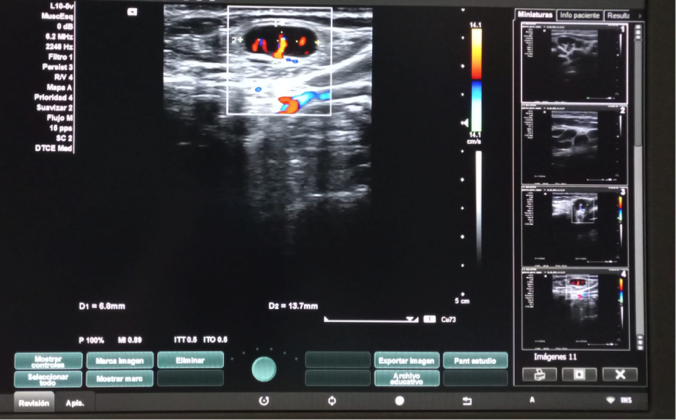

Hallazgos ecográficos

Dos adenopatías en territorio laterocervical derecho, con hilio central y doppler positivo, alguna con diámetro transversal superior al longitudinal, de probable origen reactivo y una adenopatía supraclavicular sin hilio central y con vascularización generalizada.

El diagnóstico histopatológico confirmó una linfadenitis histiocítica necrotizante, compatible con EKF, entidad benigna, poco frecuente, autolimitada y con clínica variable, pudiendo simular a patología infecciosa, trastornos linfoproliferativos y determinadas patologías reumatológicas. La clinica es en forma de adenopatías cervicales, fiebre, sudoración nocturna y mialgias. El diagnóstico es histopatológico, pero la ecografía realizada en Atención Primaria fue esencial para orientarlo, puesto que mostraba evidentes criterios de benignidad acompañados de otros hallazgos (ganglios mayores de 10 mm algunos con mas diámetro transversal que longitudinal y la presencia de una adenopatía supraclavicular) que precisaban descarte y diagnóstico diferencial de otras entidades.